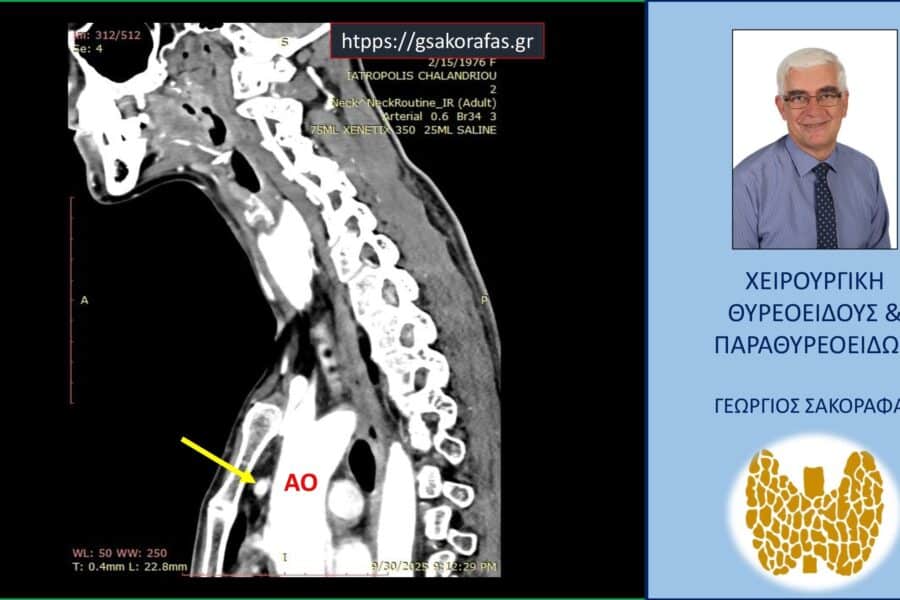

Αδένωμα Παραθυρεοειδούς Αδένωμα παραθυρεοειδούς σε έκτοπη θέση σε ασθενή μας με πρωτοπαθή υπερπαραθυρεοειδισμό – ακριβής εντοπισμός με τετραδιάστατη αξονική τομογραφία, αρνητικό υπερηχογράφημα και +/- σπινθηρογράφημα Αδένωμα παραθυρεοειδούς σε έκτοπη θέση σε ασθενή μας με πρωτοπαθή υπερπαραθυρεοειδισμό – ακριβής εντοπισμός με… George Sakorafas13 Αυγούστου 2025

Αδένωμα ΠαραθυρεοειδούςΠαραθυρεοειδεκτομήΠρωτοπαθής ΥπερπαραθυρεοειδισμόςΥπερπαραθυρεοειδισμός Επιμένων Υπερπαραθυρεοειδισμός Επιμένων Υπερπαραθυρεοειδισμός Η ασθενής, ετών 59 προσήλθε για χειρουργική αντιμετώπιση επιμένοντος πρωτοπαθούς υπερπαραθυρεοειδισμού (PTH… George Sakorafas29 Μαΐου 2025